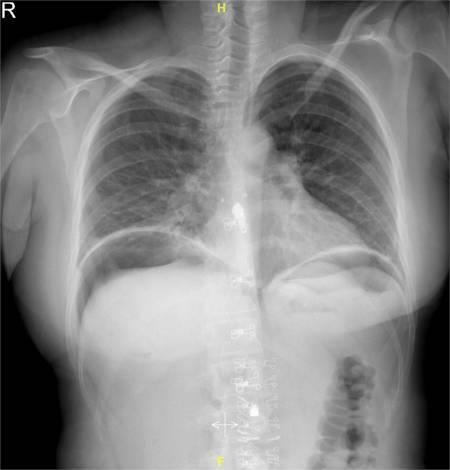

经检查,患者有心动过速和呼吸急促。然而,血压、体温和氧饱和度均在正常范围内。腹部柔软,没有膨胀,手术部位有轻微压痛。手术切口清洁干燥。对患者进行了镇痛,但生命体征没有改善。血红蛋白(Hb)水平为9g/dl,白细胞(WBC)计数为12×10%/l。电解质、肝肾功能均在正常参数范围内。在直立胸片上,横膈膜下可见气体(图1)。

图1 直立胸部X光片上横膈膜下有气体